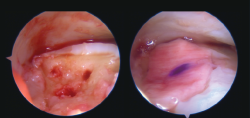

- Cirugía artroscópica: lesiones osteocondrales, tratamiento artroscópico de la inestabilidad (reparación y técnicas de reconstrucción), endoscopia posterior de tobillo y tendoscopia (Figuras 4, 5, 6 y 7).

Figura 6. Plastia de ligamento talofibular anterior (LTFA) + ligamento calcaneofibular (LCF) por vía artroscópica.